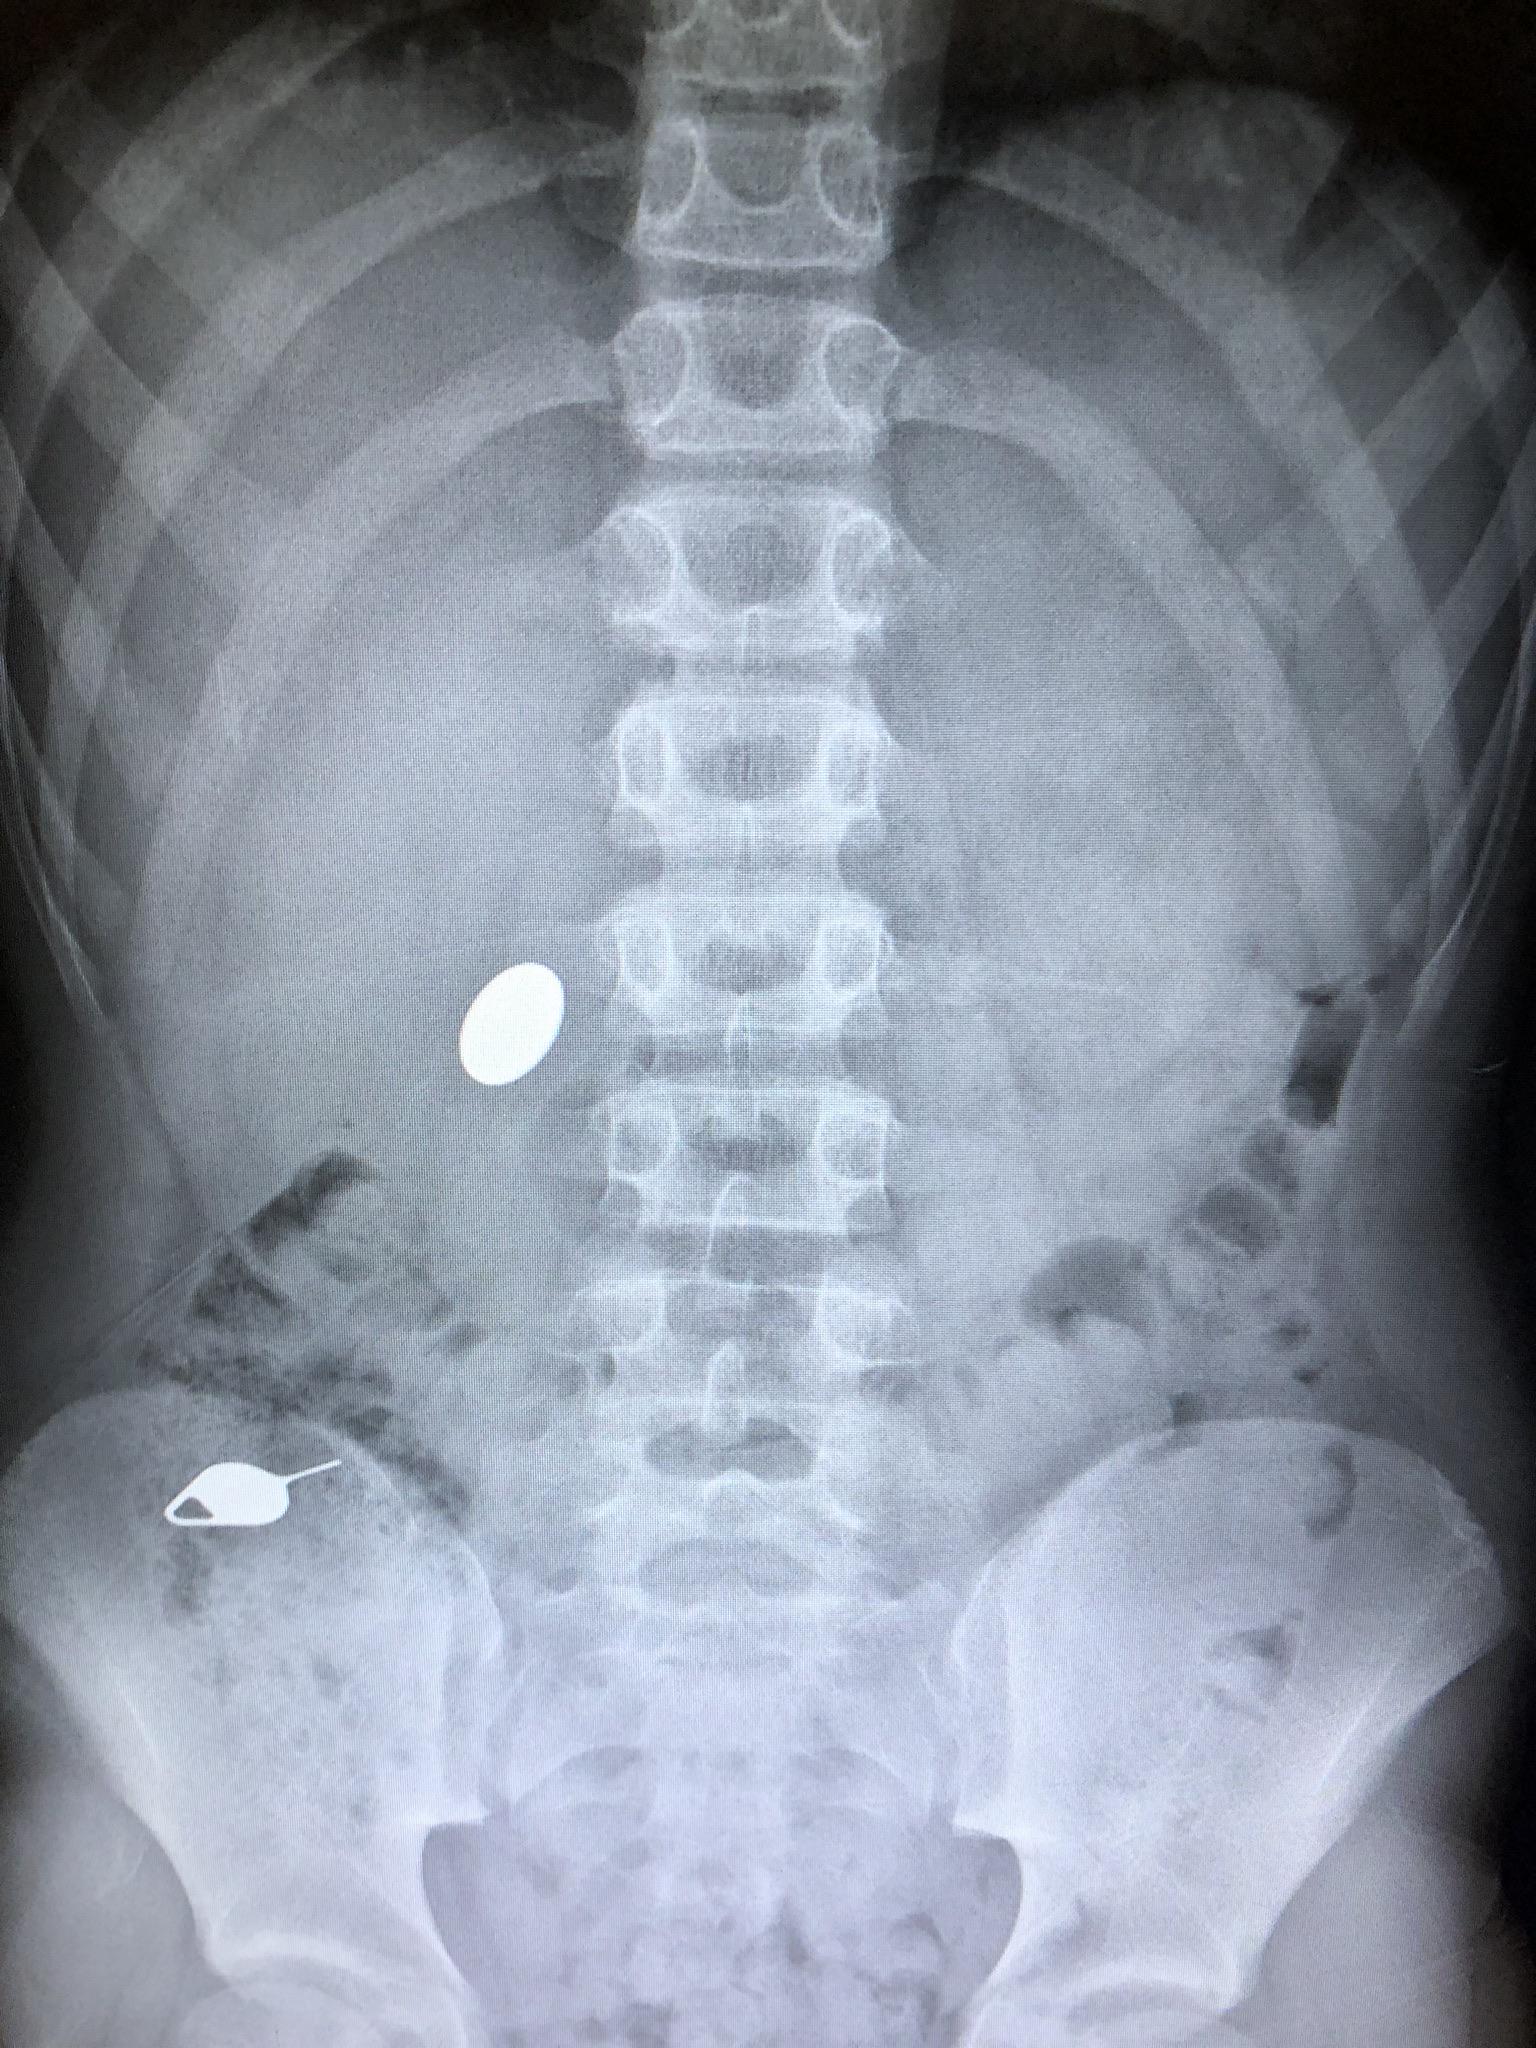

My daughter swallowed an earring r/mildlyinteresting My Baby Swallowed My Earring I’m glad baby is okay. My 8mo was chewing on a board book this evening when i noticed a bit sized chunk of it was missing. Thousands of children swallow all kinds of objects every year. Find out what to do if it happens and how to know if they need. Seek immediate medical attention if you or someone you. My Baby Swallowed My Earring.

My kid swallowed a penny while showing his little brother how he accidentally swallowed a simm My Baby Swallowed My Earring Learn more about swallowed foreign object including types of objects swallowed by children and button batteries, as. Find out what to do if it happens and how to know if they need. I’m glad baby is okay. Swallowing a magnetic object is a medical emergency. If your child swallowed a coin or another round, small, metal object, it is a. My Baby Swallowed My Earring.